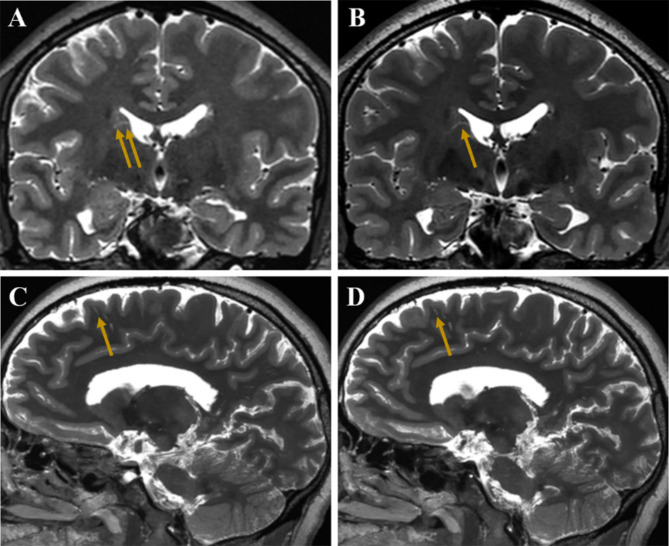

Method: A total of seventeen subjects underwent three-dimensional (3D) T1- and T2-weighted imaging on both 3-T and 5-T MRI systems. Twelve of these subjects underwent quantitative analysis of PVS in the semioval center (SOC) and basal ganglia (BG), with comparisons made between the two systems using paired-sample Wilcoxon tests. Additionally, high-resolution 5-T images were acquired for five other participants to examine the detailed anatomy of PVS in the SOC, BG, and cerebral cortex.

Results: Compared with 3-T MRI, 5-T MRI detected more PVS in the SOC and BG [39.5 (32.0-63.0) vs. 56.5 (44.0-75.5) and 49.5 (27.0-55.8) vs. 65.5 (53.0-72.0)] with p-values of 0.002 and 0.004, respectively. In these two regions, the PVS tortuosity, defined as the ratio of the actual path length to the straight-line distance between the start and end points of the PVS, was lower at 3-T compared to 5-T (p = 0.012 for the SOC and p = 0.006 for the BG). The length of PVS in the SOC on 5-T was longer than those on 3-T [4.6 mm (3.9-6.3 mm) vs. 5.1 mm (4.6-6.7 mm), p = 0.049]. In addition, the 5-T MRI provided enhanced visualization of the morphology of PVS in vivo, and improved the depiction of PVS across various brain regions, especially in the cortex, illustrating their course and associated small vessels.

Conclusions: 5-T MRI notably enhanced the visualization of PVS compared to 3-T, particularly in its ability to depict PVS anatomy in the cortex using high-resolution images. This advancement may pave the way for further research into the physiological roles of PVS and their involvement in related diseases.